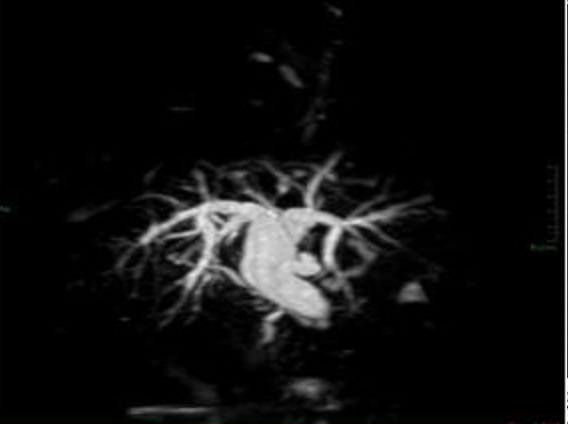

Image TDM du

foie en coupe axiale ( avec produit de contrast

intraveineuse ) |

Image TDM de meme cas par

recontruction en coupe coronale ( frontale ) . Image

de aorte abdominale , artere mesenterique superieure

, veine cave inferieure , veine porte et sa branche

se voyaient nette |

Image de recontruction spaciale de

aorte abdominale et ses branches en 2D et 3D